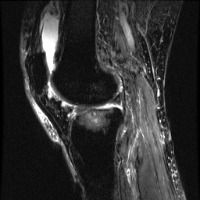

meniscal Computer Vision Project

Medical Diagnostics: Radiologists, orthopedic surgeons, and other medical professionals can utilize the "meniscal" model to accurately identify and classify meniscal lesions in knee MRI scans, thus improving the diagnosis and treatment process for patients with knee-related injuries and conditions.

Sports Injury Prevention and Management: Sports rehabilitation centers and athletic trainers can employ the "meniscal" model for analyzing knee scans of athletes to assess the health of their knees, track any changes over time, and tailor training regimens or treatments to prevent or recover from meniscal injuries.

Pre- and Post-Surgery Evaluation: Surgeons can use the "meniscal" model to analyze the knee scans taken before and after meniscal surgeries to evaluate the efficacy of the surgical intervention and make informed decisions about the patient's further treatment plan and rehabilitation process.